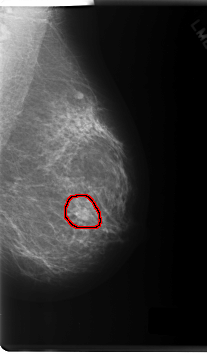

C_0165_1.LEFT_MLO

FILE: C_0165_1.LEFT_CC.OVERLAY

TOTAL_ABNORMALITIES 1

ABNORMALITY 1

LESION_TYPE MASS SHAPE ROUND MARGINS SPICULATED

ASSESSMENT 5

SUBTLETY 5

PATHOLOGY MALIGNANT

TOTAL_OUTLINES 1

BOUNDARY